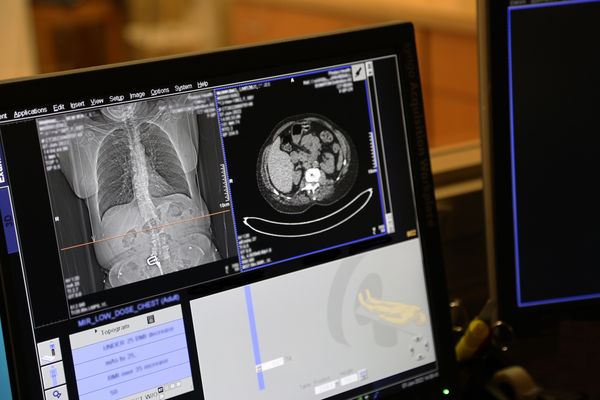

Diagnostikimi i saktë është themeli i trajtimit modern. CT-ja e gjoksit është metoda më e rëndësishme në zbulimin e masave tumorale, ndërsa PET-CT mundëson vlerësimin e përhapjes së sëmundjes në të gjithë trupin. Radiografia e mushkërive është shpesh e pamjaftueshme, sepse shumë tumore “fshihen” pas strukturave të zemrës ose brinjëve.